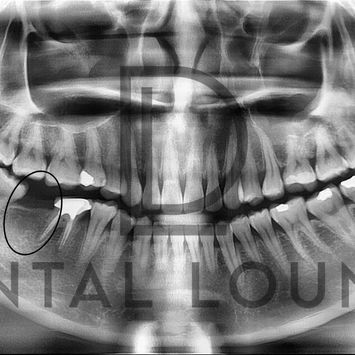

Implant Placement at #47 with Limited Access Due to Restricted Mouth Opening

Missing lower right second molar (#47) requiring implant replacement.

Edentulous #47 site

CBCT showed adequate bone for implant placement

Limited mouth opening noted, posing challenges for access and bone preparation

Pre-operative Assessment

CBCT reviewed

Implant position planned